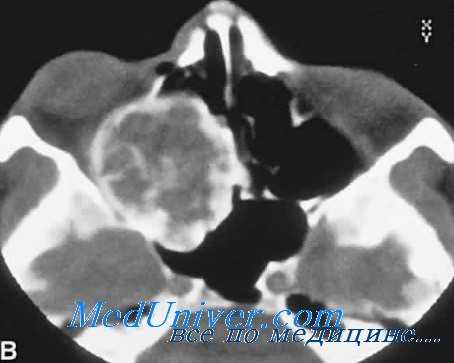

Липома глаза на компьютерной томограмме